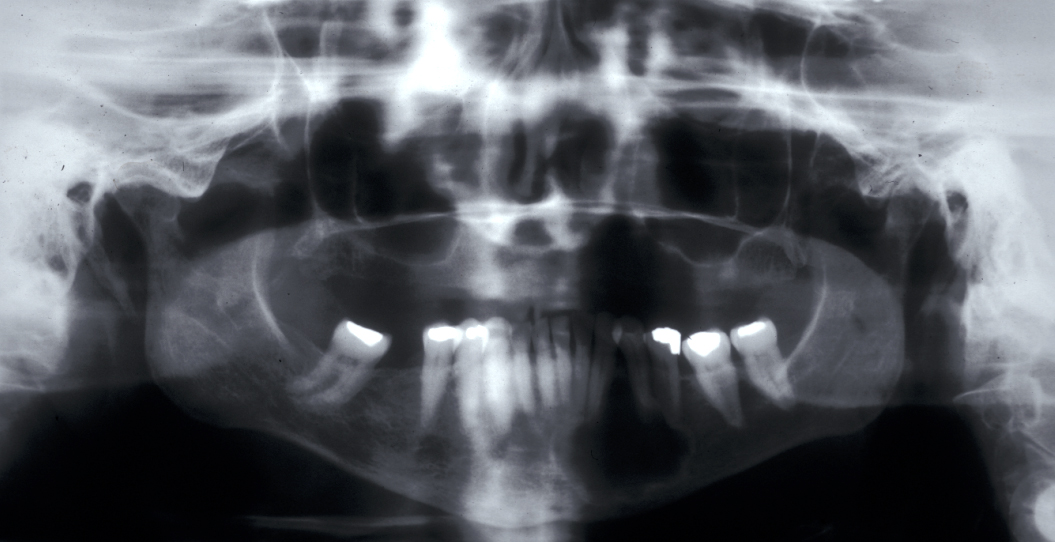

Radicular cyst – in a non-vital tooth, this cyst appears as a rounded periapical radiolucency in an X-ray radiograph, with loss of lamina dura (bone surrounding the tooth socket) and a sclerotic margin if it is a long-standing lesion. Figure 1 shows an example.

Dentigerous cyst – usually found as an incidental finding on radiographs. The cyst envelopes the crown of a tooth. Lower third molars (wisdom teeth) are most frequently affected, followed by upper canines and lower premolars.

Keratocyst / keratoystic odontogenic tumour (KOT) – this cyst is thought to replace a missing tooth (may be a supernumerary). It is associated with unerupted teeth in 40% of cases. It appears radiographically as a uni- or multiloculated radiolucency with a well-defined sclerotic margin. These cysts tend to grow in an antero-posterior direction and therefore do not always cause bony expansion.

Radiographically, aneurysmal bone cysts form unilocular (consisting of a single chamber) or multilocular (consisting of multiple chambers) radiolucencies, which can be mistaken for ameloblastoma or keratocysts (see above).

Clinically, solitary bone cysts are usually asymptomatic but there is occasionally bone expansion and radiographically there is an irregular radiolucency with well-defined scalloping between the roots of the teeth. Histological examination shows a thin layer of loose vascular fibrous tissue but no epithelial lining and there is no cyst fluid.